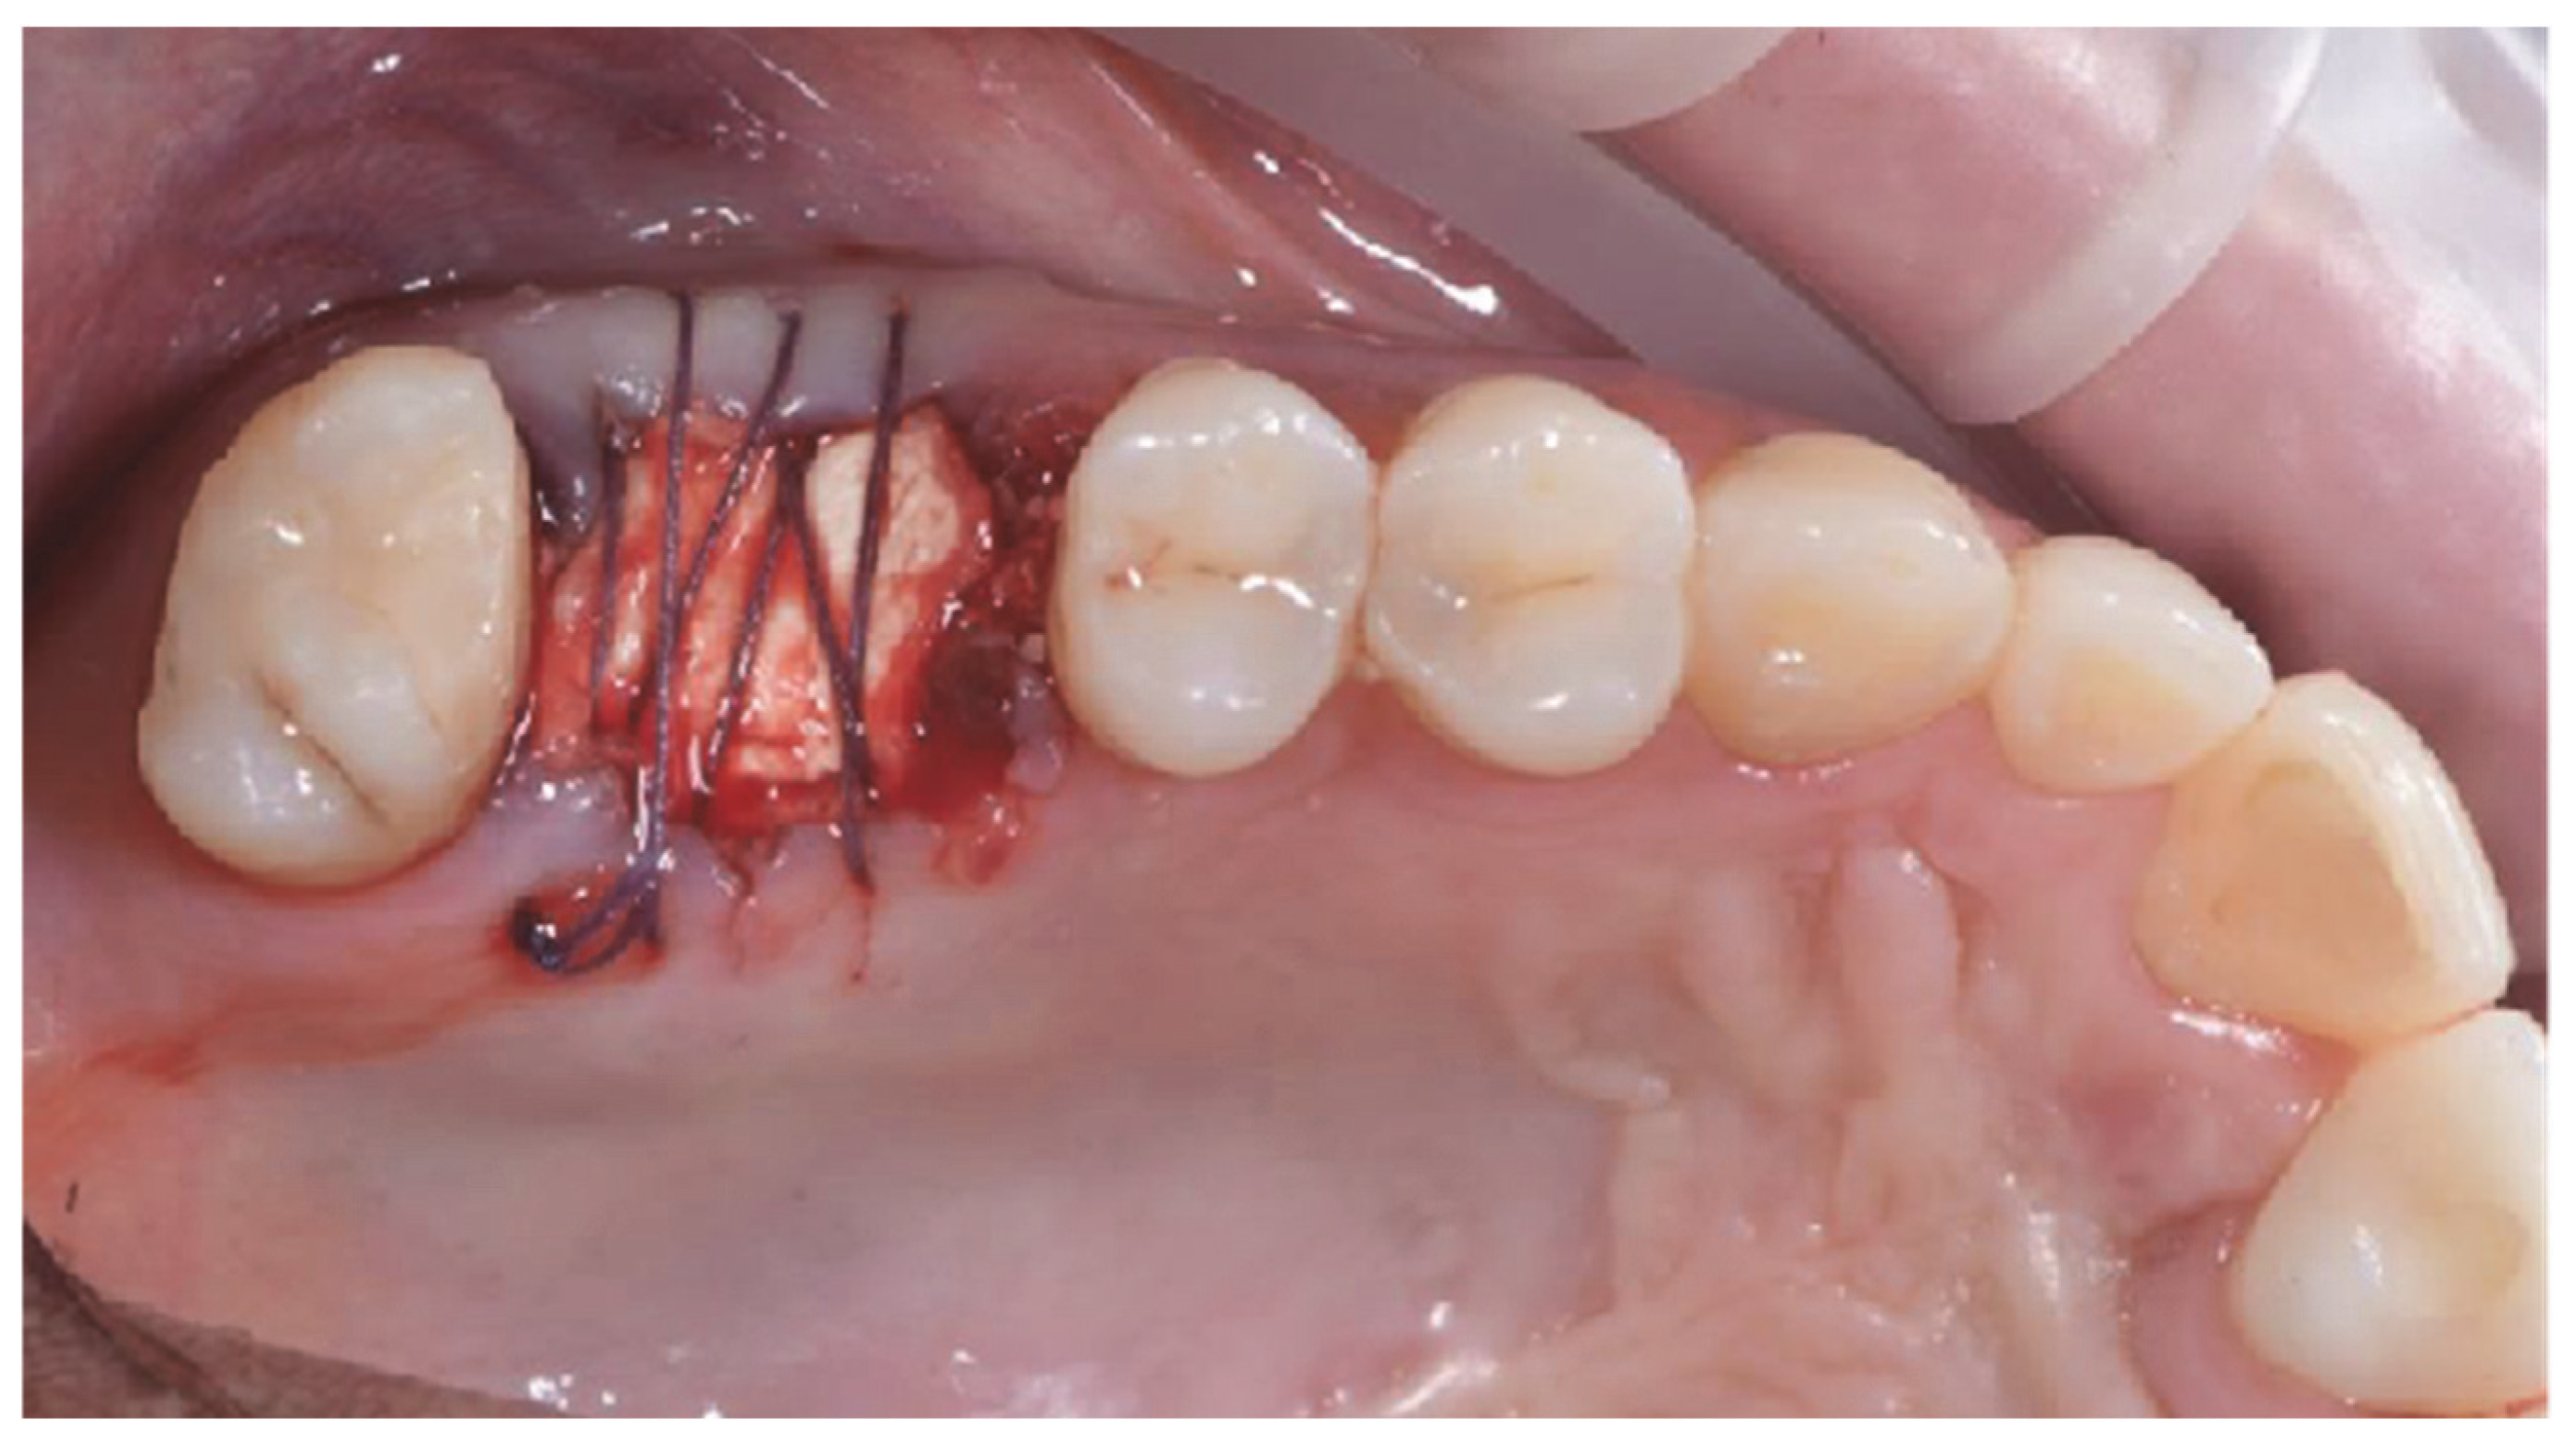

2.1. Socket Preservation Procedure

2.2. Post-Surgical Instructions and Prosthetic Phase After Socket Preservation